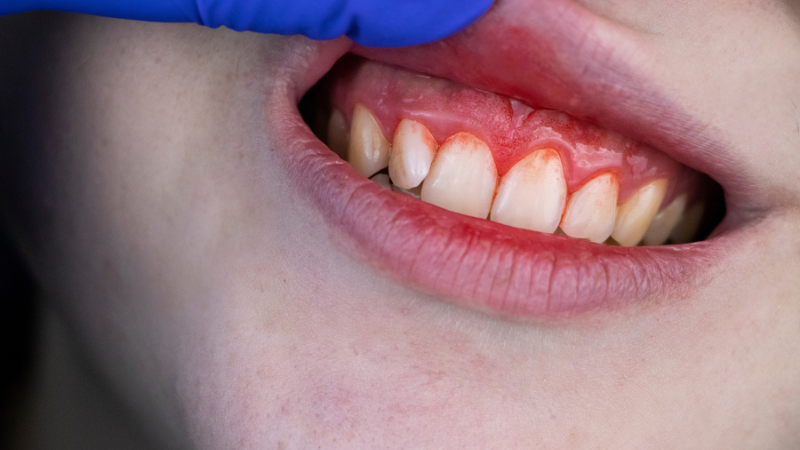

初期段階(歯肉炎)では「歯茎が少し赤い」「ブラッシング時に出血する」程度の症状ですが、進行するにつれて歯茎が大きく腫れ、痛みを伴うこともあります。

・歯茎がぷよぷよと柔らかくなっている

・歯茎の色が赤みや紫みを帯びている

・触れると出血する

・口臭が強くなった気がする

・歯が以前より長く見える(歯茎が下がってきた)

痛みのない症状ほど発見が遅れやすいのが歯周病の特徴です。「痛くないから大丈夫」と思わず、症状に気づいたら歯科への相談をおすすめします。